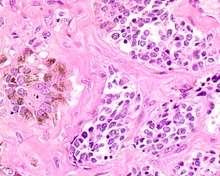

The tumor is usually very well circumscribed but not encapsulated. There are two cell types present (biphasic), arranged in alveolar or tubular configurations.

There are centrally located, small, darkly staining cells comprising the majority of cells. These cells have a fibrillary cytoplasm surrounding round nuclei with coarse and heavy nuclear chromatin. These cells are surrounded by much larger polygonal cells that have open nuclear chromatin and abundant opaque cytoplasm that has granular melanin pigment.

There is usually no hemorrhage, necrosis or increased mitoses. [1][3]